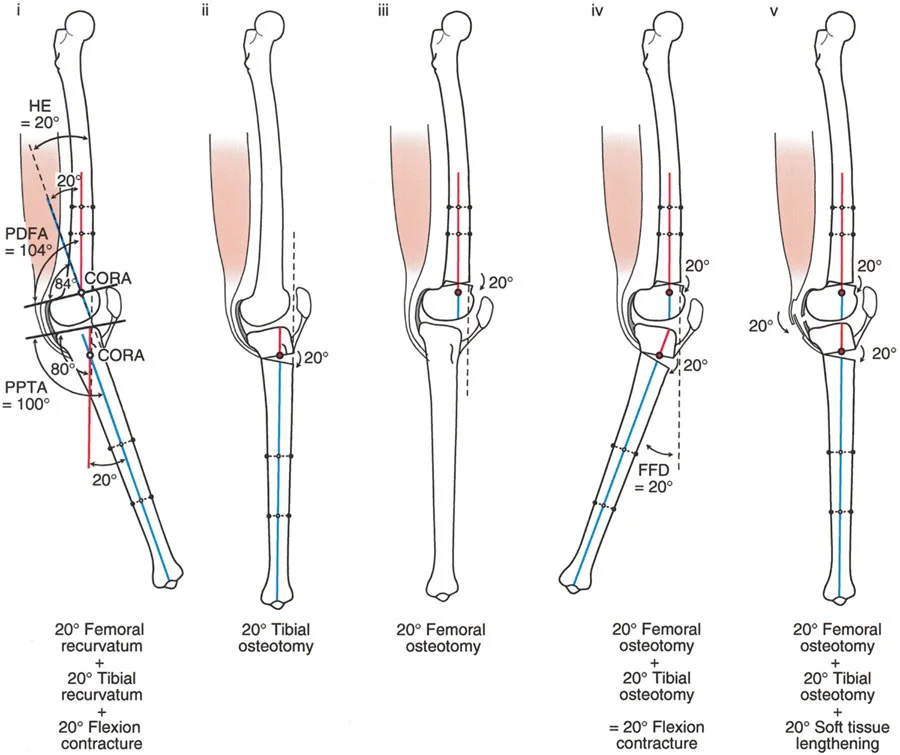

- على سبيل المثال، قد يؤدي توقف النمو الجزئي في عظم الفخذ البعيد إلى تشوه ارتدادي فخذي بمقدار 20 درجة، مما يسبب فرط تمدد الركبة.

- على الرغم من أن الركبة الارتدادية هي فرط تمدد، إلا أنه في بعض الحالات، يمكن أن يترافق التشوه العظمي بتقلص في الأنسجة الرخوة يحد من انثناء الركبة. هذا التقلص يمكن أن "يخفي" أو "يعوض" جزئيًا فرط التمدد العظمي، مما يجعل الركبة تبدو في وضع تمدد طبيعي ظاهريًا.

- على سبيل المثال، إذا كان هناك ارتداد فخذي بمقدار 20 درجة مع تقلص انثناء 20 درجة، فقد تبدو الركبة في وضع تمدد كامل (0 درجة) ولكنها تعاني من فقدان في مدى الانثناء.

- زاوية الانحناء البعيدة للفخذ (PDFA - Posterior Distal Femoral Angle): تقيس زاوية الجزء السفلي من عظم الفخذ. القيمة الطبيعية حوالي 84 درجة. الزيادة في هذه الزاوية (أكثر من 84 درجة) تشير إلى ارتداد فخذي.

- زاوية الانحناء القريبة للظنبوب (PPTA - Proximal Posterior Tibial Angle): تقيس زاوية الجزء العلوي من عظم الساق. القيمة الطبيعية حوالي 80 درجة. الزيادة في هذه الزاوية (أكثر من 80 درجة) تشير إلى ارتداد ظنبوبي.

- مركز دوران الزاوية (CORA - Center of Rotation of Angulation): يتم تحديد هذا النقطة على الأشعة السينية لتحديد مكان التشوه العظمي بدقة، وهو أمر بالغ الأهمية لتخطيط عملية قطع العظم.

- الركبة الارتدادية بسبب الارتداد الفخذي:

- إذا كانت درجة فرط التمدد (HE) تساوي درجة الارتداد الفخذي (PDFA > 84°)، فهذا يعني أن التشوه كله ناتج عن عظم الفخذ.

- في هذه الحالة، يكون مركز CORA في الجزء البعيد من عظم الفخذ.

- الركبة الارتدادية بسبب الارتداد الفخذي مع تقلص انثناء:

- إذا كان هناك ارتداد فخذي (PDFA > 84°) ولكن لا يوجد فرط تمدد سريري (HE = 0°)، فهذا يشير إلى وجود تقلص انثناء مصاحب يعوض التشوه العظمي.

- إذا كان فرط التمدد (HE) أقل من درجة الارتداد الفخذي، فهذا يعني وجود تقلص انثناء جزئي.

- الركبة الارتدادية بسبب الارتداد الظنبوبي:

- إذا كانت درجة فرط التمدد (HE) تساوي درجة الارتداد الظنبوبي (PPTA > 80°)، فهذا يعني أن التشوه كله ناتج عن عظم الساق.

- في هذه الحالة، يكون مركز CORA في الجزء القريب من عظم الساق.

- الركبة الارتدادية بسبب الارتداد الظنبوبي مع تقلص انثناء:

- إذا كان هناك ارتداد ظنبوبي (PPTA > 80°) ولكن لا يوجد فرط تمدد سريري (HE = 0°)، فهذا يشير إلى وجود تقلص انثناء مصاحب.

- إذا كان فرط التمدد (HE) أقل من درجة الارتداد الظنبوبي، فهذا يعني وجود تقلص انثناء جزئي.

- الركبة الارتدادية بسبب تشوه مركب (فخذي وظنبوبي):

- إذا كان هناك ارتداد في كل من الفخذ والساق، وكان مجموع درجتي الارتداد يساوي درجة فرط التمدد الكلي للركبة.

- إذا كان هناك تشوه مركب مع تقلص انثناء مصاحب، فقد يكون فرط التمدد السريري أقل من مجموع التشوهات العظمية.

أ. قطع العظم الفخذي لتصحيح الارتداد الفخذي:

- متى يتم إجراؤها: عندما يكون التشوه الرئيسي في عظم الفخذ البعيد.

- الإجراء: يتم إجراء قطع للعظم (عادة قطع عظم انثناء) في الجزء البعيد من عظم الفخذ، عند مركز دوران الزاوية (CORA)، لإعادة محاذاة العظم.

- الهدف: تصحيح فرط تمدد الركبة واستعادة المحاذاة الطبيعية.

- مثال: لتصحيح ارتداد فخذي بمقدار 20 درجة، يتم إجراء قطع عظم انثناء فخذي بمقدار 20 درجة.